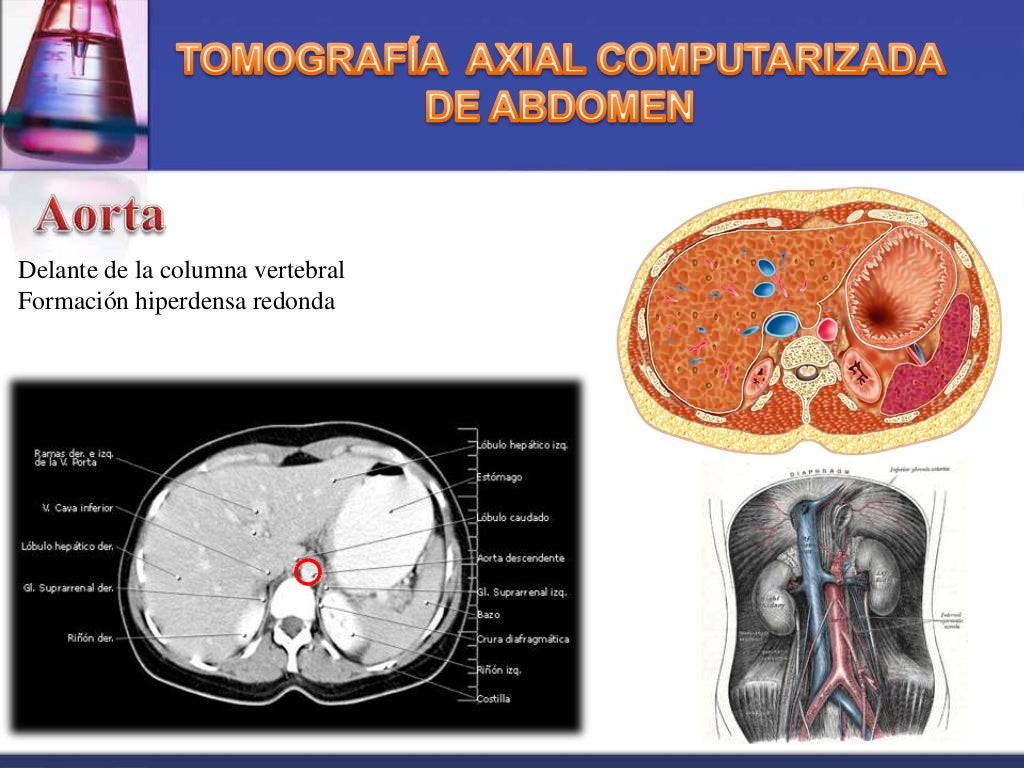

Tomografía de abdomen con doble contraste, en corte coronal, que

Tomografía de abdomen con contraste. Download Scientific Diagram

Tomografía Axial Computarizada (TAC) del abdomen que muestra una